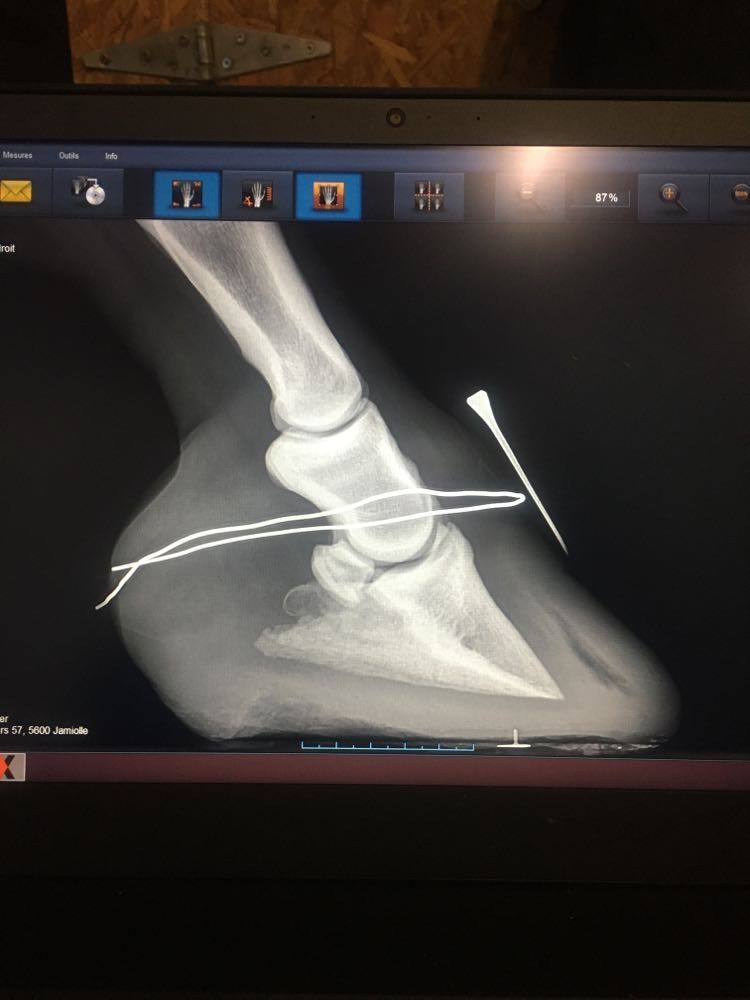

DéconnectéDire merci | muesli08 Au sujet des radios, oui je les ai vues. Est ce que vous pourriez poster toutes les radios et peut être obtenir de votre vétérinaire les radios sans notation écrite dessus car elles masquent une partie des radios, en particulier elles empêchent de voir clairement l'épaisseur de la sole? Certainement qu'en discutant avec Remco, il vous a précisé les points importants du parage de réalignement, dont le fait, dès le premier parage de raccourcir la pince de façon à ramener le point de bascule à sa vraie position c'est à dire juste devant la vraie ligne blanche ( pour corriger l'angle dorsal ) et de faire un chanfrein en pince et sur tout le pourtour du pied ( pour supprimer les forces de séparation exercées sur les lamelles affaiblies/la paroi du sabot par le poids du cheval et permettre à la nouvelle paroi qui pousse à partir de la bande coronaire de pousser dans le bon angle parallèle à la face dorsale de P3). Les talons doivent être abaissés pour restaurer un angle palmaire autour de 5 degrés. Je ne vois pas bien à cause des inscriptions sur la radio mais la sole ne semble pas très épaisse sous la pointe de P3; il est important que la sole se développe à cet endroit et donc les talons doivent être abaissés qu'à partir de la hauteur de la fourchette, ce qui va laisser le pied en 2 plans au niveau de sa surface solaire, le temps que la sole se développe à l'avant du pied mais ce n'est pas grave si les piesds sont bien soutenus dans des boots avec des semelles épaisses à l'intérieur. J'essaie de vous faire des tracés sur les radios pour que cela soit plus clair si vous le souhaitez et de vous envoyer des infographies sur le sujet. |

| Dire merci | ![]() voilà j'ai réussi et oui j'ai lu sur la page TLS Elle a déjà eu un premier parage avant radio où les talons ont été baissé une bonne fois (je pense qu'il avait retiré plus d'1/2 cm, les talons étaient à 25mmm, depuis je l'ai descendue à 20mm jusqu'au plan de la sole, avec chanfrein et la pince avait bien été reprise également pour retirer la pression lamellaire, c'est d'ailleurs après ce premier parage à J11 qu'elle s'est sentie beaucoup mieux ! |

| Dire merci | bon je viens donner des nouvelles ! radios de mercredi : ![]() ![]() la rotation es déjà bien corrigée là il me reste à rétablir un point de break over parfait : surtout sur base de la punaise à l'apex qui me permettra de couper pile poil où il faut. ça repousse , lentement ne pince, plus vite en talons ce qui donne de précieuses indications : que je dois surveiller la hauteur de talons chaque semaine et les garder à hauteur de la sole en permanence. Muesli n'est plus du tout sensible sur sol souple !!! Elle garde tout de même ses chaussures et semelles en permanence : vu la poche de gaz , je dois me méfier , la laisser marcher sans soutien pourrait accentuer la bascule. je pare les prochains jours (j'attends les mark ups, j'ai bien ma petite idée, mais je ne peux me permettre d'être approximative. ) édit car j'oublie toujours de refermer les parenthèses que j'ouvre et aussi pour vous dire : regardez comme la sole s'est épaissie sous la pointe de p3 en 3 semaines !! Message édité le 06/12/20 à 19:33 |

En ligneDire merci | la sold a bien repris c’est top et la deuxième radio l’alignement est pas mal du tout tu as vraiment de quoi reprendre en talon et en pince en plus. les poches de gaz vont partir avec la reprise en pince sur tes parages c’est douloureux donc fais gaffe à bien garder le pied dans des boots . maintenant c’est surtout le pied de la première radio à travailler pour reprendre l’alignement mais c’est vraiment nettement mieux |